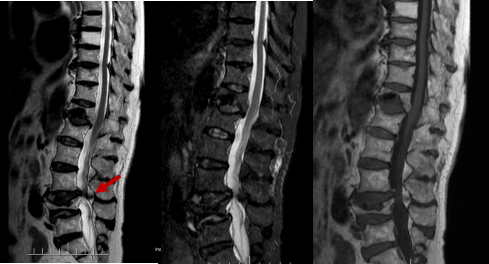

箭头所示病灶位置

然而病情并没有家属想象中简单,检查结果显示梁婆婆右侧耻骨上下支骨折、腰椎椎管狭窄,却未发现胸腰椎新鲜压缩骨折。经冯学烽主任、杨立进主治医师查体发现,婆婆还伴有臀、腿麻木症状。

冯学烽主任表示,综合检查结果和临床症状,考虑梁婆婆是摔倒后椎管压迫脊髓加重损伤,单纯治骨盆骨折无法解决行走问题,需要做传统的腰椎的开放减压内固定手术才能从根本上解决问题。